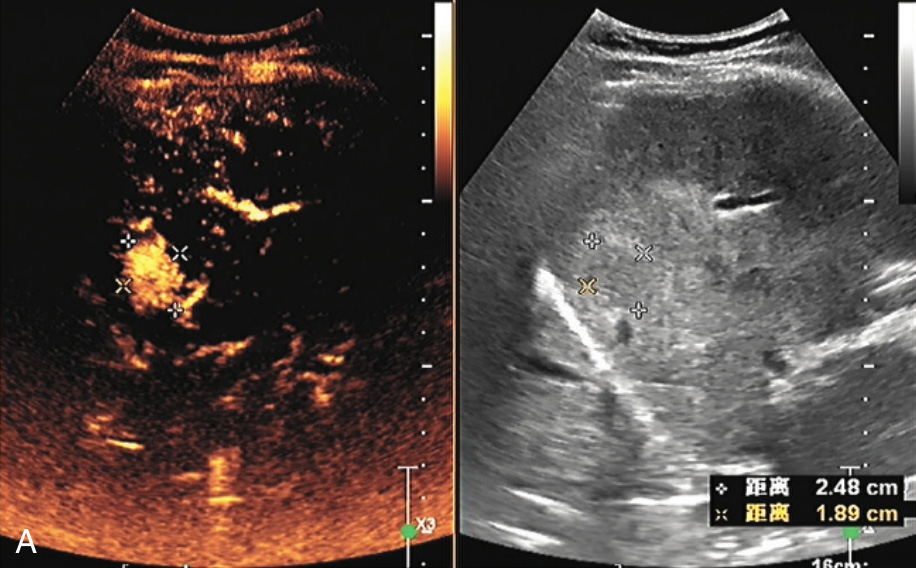

图1-5-2 肝细胞腺瘤超声造影图像

A.动脉期病变快速增强,病灶周边有灌注的环状高回声并伸入病灶内部